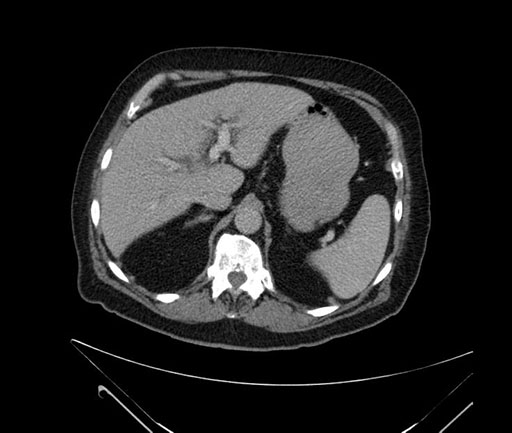

Imaging Analysis

Look through the patient's CT scan to identify any areas of concern for the necessary procedure.

Based on your CT findings, which issue(s) would give reason for "planned slowing down moment(s)" in this case?